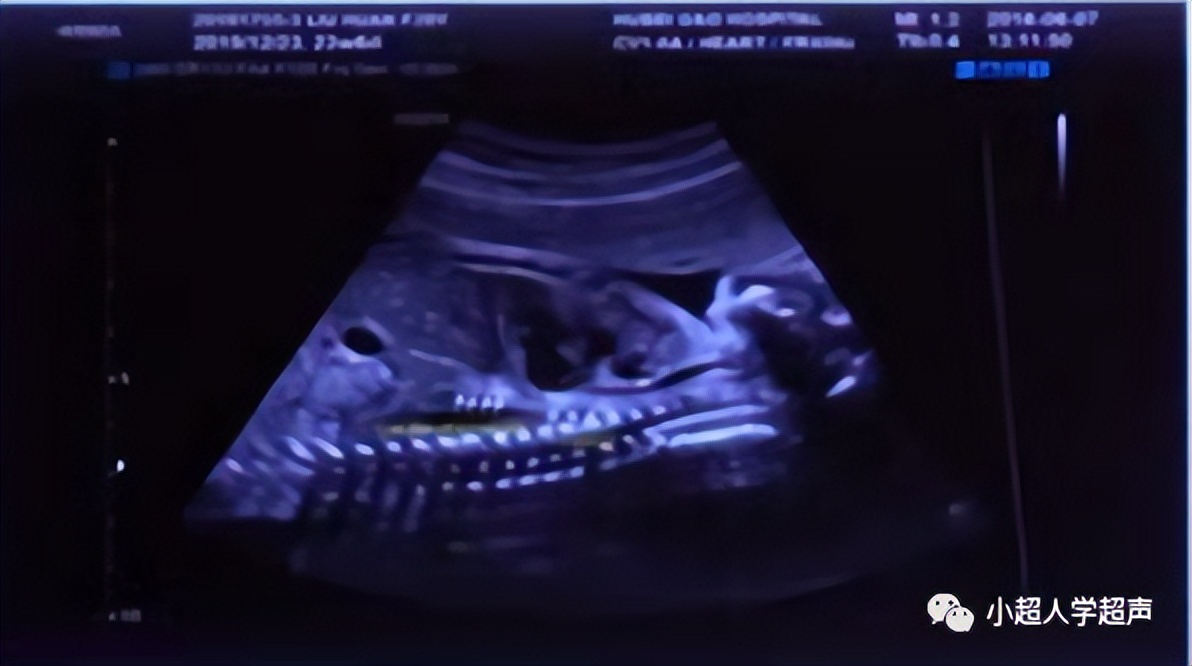

超声表现为四条线状高回声,代表食道的前后壁。食道内因胎儿吞咽偶尔可见液体,因而可显示为一根细小的管道。

由于食道并不成一条直线,多数情况下显示整体结构比较困难。颈部、胸部和腹部部分可分别显示。

直接征象 :食道盲端的囊袋征,胎儿颈部的囊性结构

产前超声很难显示食管闭锁部位,所以很难进行准确的分型,常常通过羊水过多、胃泡不显示、腹围小等一些间接征象并动态观察胎儿吞咽羊水时是否出现颈部的“囊袋样”无回声来提示食管闭锁,因此产前超声对食管闭锁的检出率各家报道不一,大多不超过50%。

- 颈段食道在矢状面显示最佳

- 胸段则在气管后面,与气管平行

- 最远端的腹部部分偏离脊柱,在胃的入口处可以看见。